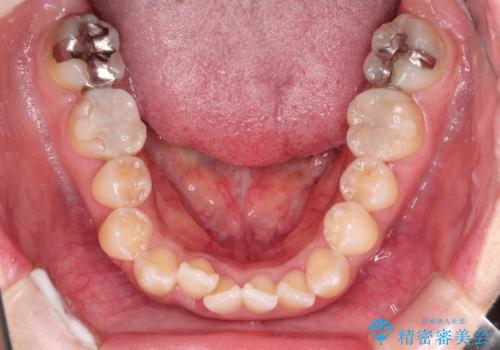

前歯のガタつきをマウスピース矯正で改善! 驚きの効果を体験しよう

- 前歯のガタツキが気になると来院されました。

マウスピース矯正治療を選択しました。

奥歯の噛み合わせは綺麗に噛んでいたため、前歯の叢生(でこぼこ)に集中して治療するように計画しました。

奥歯の噛み合わせは整っていたため、前歯の並びを美しく修正することに専念できました。